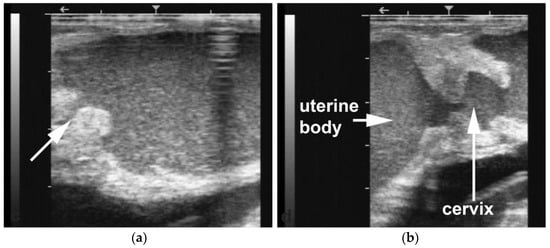

Hydrobursitis, or ovariobursitis, is a peculiar disorder in camels characterized by the accumulation of varying amounts of fluid within the ovarian bursa [44]. This pathology has been reported worldwide but appears to have a higher incidence in the Middle East [1,23,34,37,44,45]. The etiopathogenesis remains unclear. However, based on biochemical analysis of the fluid content, in some cases, the cause is attributed to recurrent ruptures of hemorrhagic follicles [44,46]. A variety of bacteria have been isolated (Actinobacillus spp., Escherichia coli, Klebsiella pneumoniae, Pseudomonas aeruginosa, Staphylococcus spp., and Streptococcus spp., as well as others) [46,47,48]. More recently, Chlamydophila abortus (Chlamydia abortus) infection has been demonstrated in several cases of hydrobursitis [49]. The role of Chlamydia spp., Brucella spp., and Campylobacter spp. in this pathology merits further investigation. Clinically, hydrobursitis is suspected when uterine retraction is not possible despite normal size of the uterus and cervix. Confirmation is easily obtained by transrectal or transcutaneous inguinal ultrasonography (Figure 6). Bilateral development is more frequent in females with long-standing infertility (more than 2 years) [44]. The main signs include repeat breeding, early embryo loss, and abortion [1,14,44,45]. Endometritis, uterine adhesions, and pyometra may also be diagnosed in cases of hydrobursitis [14,36,46]. Treatment with oxytetracycline (20 mg/kg IM for 7 days) combined with intrauterine infusion of metacresol sulfonic acid and formaldehyde solution was shown to be effective in restoring fertility if the lesion is small (<3 cm) [50]. Surgical excision of the affected side is the only treatment for large lesions (Figure 7) [44].

Figure 6. Ultrasonographic images of hydrobursitis in camels. (a) Arrow: echogenic fluid within the bursa; (b) Arrow: abnormal ovary contained in the fluid-filled bursa.